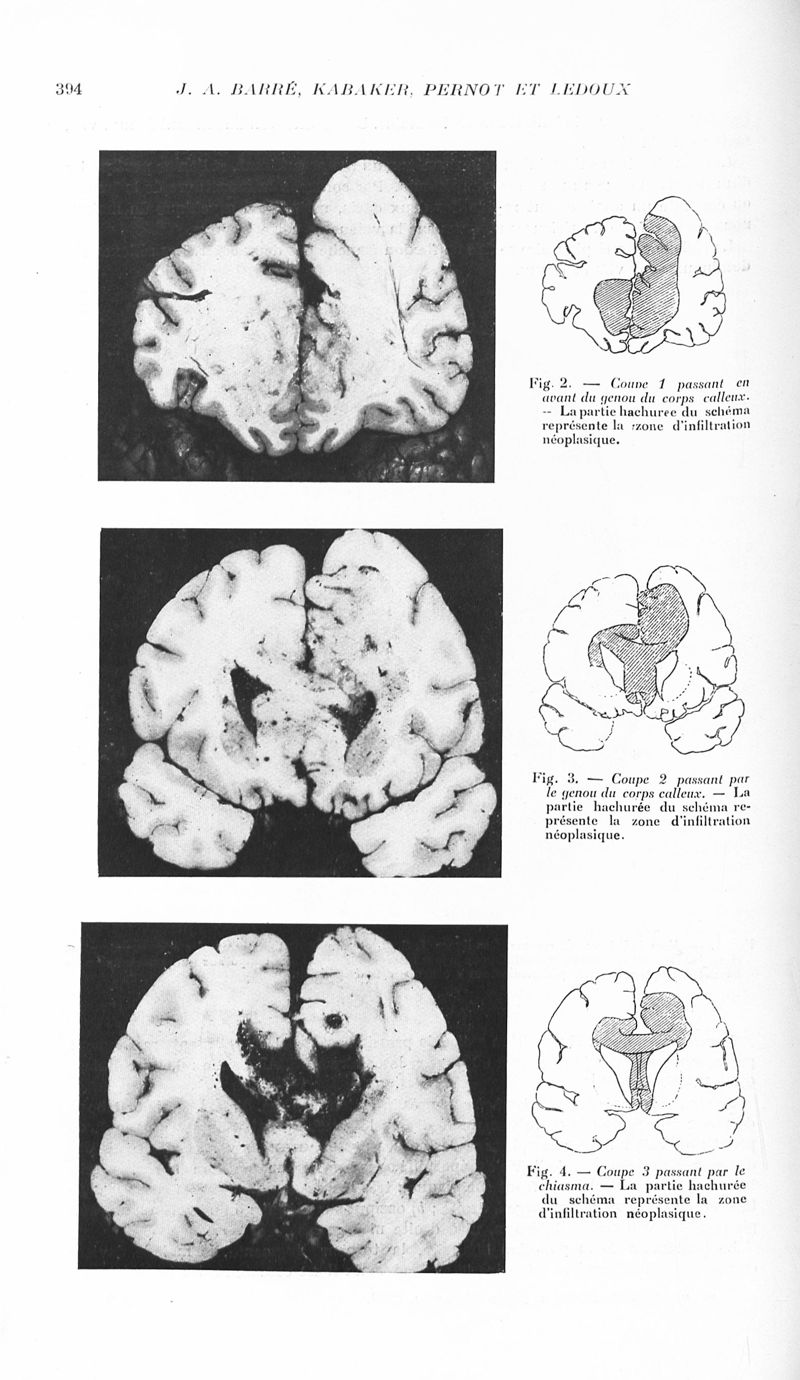

Revue neurologique

1939, vol 1. - Paris : Masson , 1939.